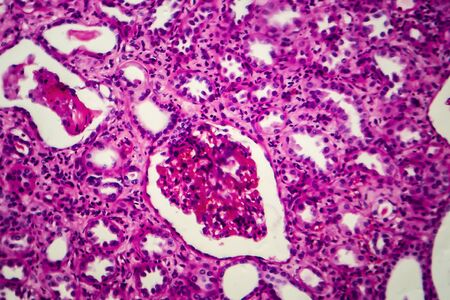

Chronic pyelonephritis, light micrograph, photo under microscope